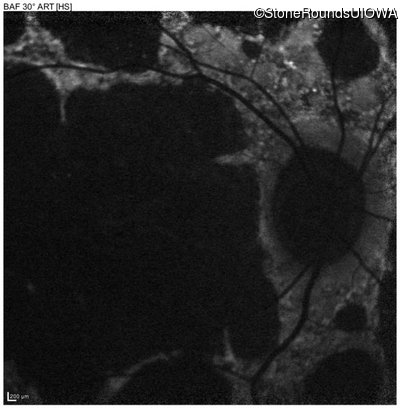

Blue Autofluorescence - Left - 10/125 +1 sc

Exemplar